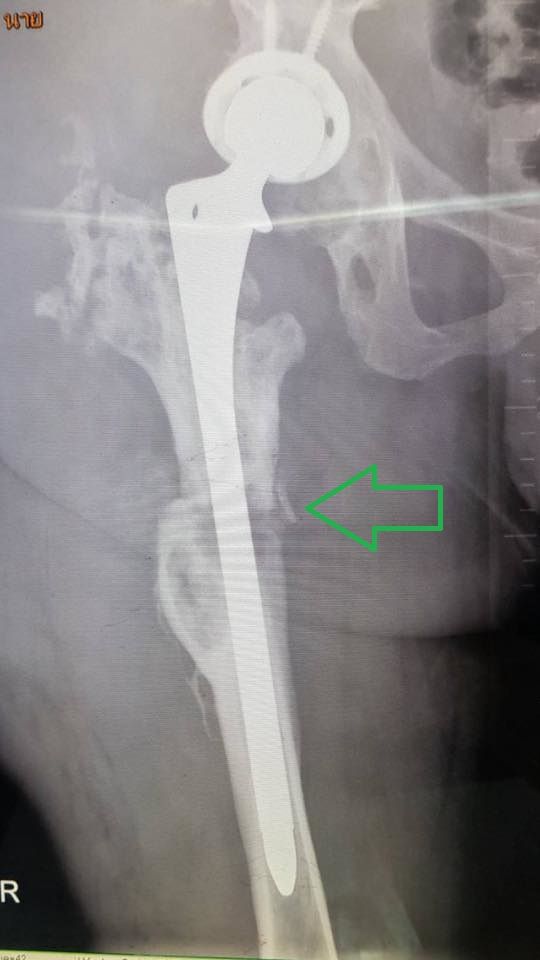

15:50 น. คุณหมอทิพชาติมาแล้ว เข้ามาบอกผล x-ray โอเคดี สะโพกเข้าที่ไม่หลุด

จากภาพคือข้อสะโพกเทียมอันใหม่ยาวกว่าเดิมอีกฝัง

ลงลึกไปกว่าเดิมจากอันเดิม

*เหล็กของเดิมยาวแค่ถึงตรงลูกศร

มารอบนี้ลงลึกไปอีกเกือบเท่านึง

(หมอบอกเอาชัวร์ๆไว้ก่อน) ไม่ได้ใช้ซีเมนต์ด้วยเลยต้องพักฟื้นนานหน่อย